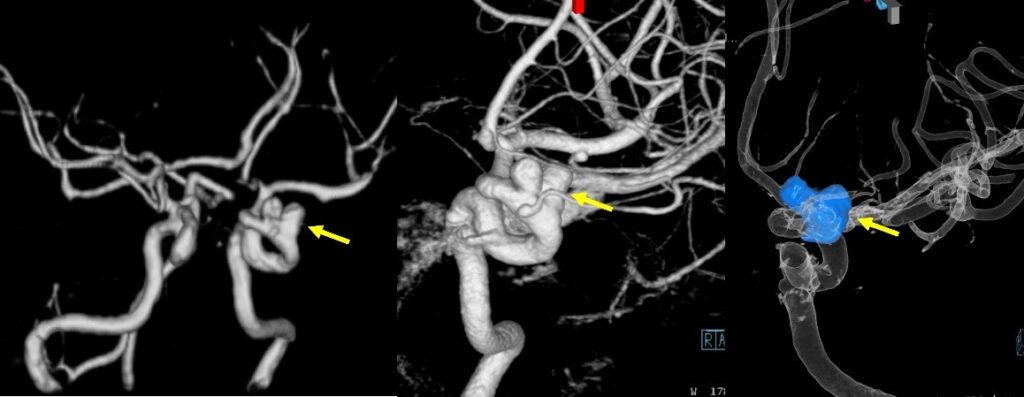

図の説明:左:脳ドックで左内頚動脈にふたこぶの動脈瘤が発見された(矢印)。中:カテーテル血管撮影の3次元撮影でふたこぶの動脈瘤の詳細を検討し(矢印)、コイルによる血管内治療を行うことにした。右:コイルを充填された後のカテーテル血管撮影3次元画像。コイルは青色で示されている(矢印)。